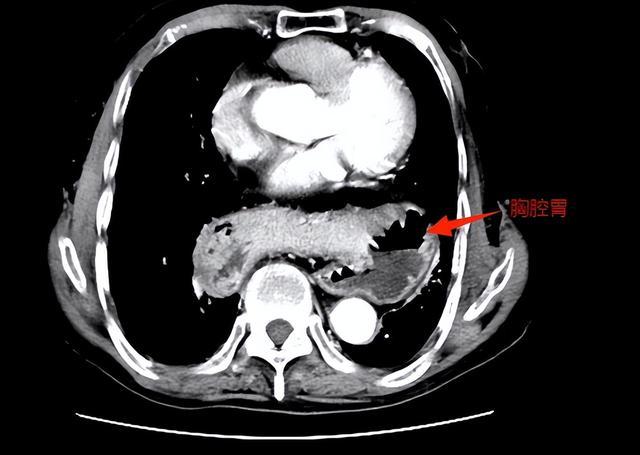

82岁的王爷爷来自湖南岳阳,两三年前开始出现烧心(平躺时尤甚)和进食后呕吐的情况,在当地医院接受护胃、补液等对症治疗,效果甚微。2025年初,老人腹痛、呕吐症状加剧,CT检查发现:他整个胃腔及部分横结肠“顶入”胸腔,形成“胸腔胃”。

▲术前,胃及横结肠“顶入”胸腔